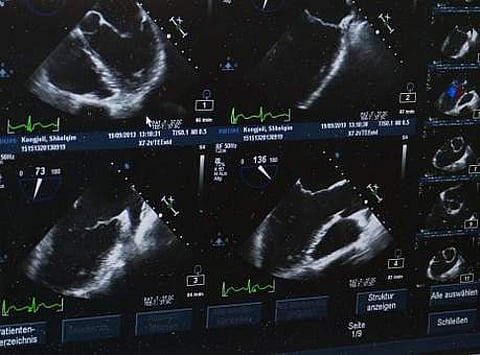

"Liver cancer screening in patients with chronic liver disease has traditionally been performed using an abdominal ultrasound. While ultrasound is readily available and noninvasive, it misses many cancers when they are small," said Amit Singal, associate professor at the University of Texas Southwestern Medical Centre.